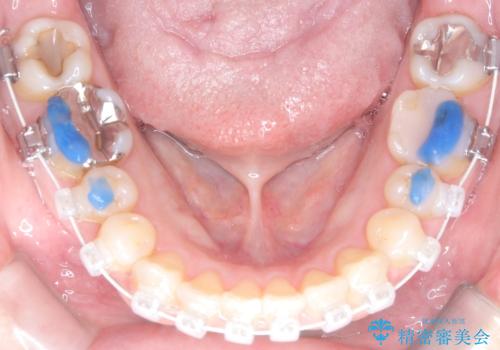

スペースを確保するために抜歯を行う選択肢もありましたが、歯列の幅や骨格とのバランスから判断し、上顎の奥歯を後方に移動させることでスペースを作る方針を立てました。そのため、まずリンガルアーチ(内側に装着する固定式装置)を用いて奥歯を遠心移動させ、その後ワイヤー矯正で歯列全体を整える治療計画を立案しました。

初期段階では、リンガルアーチを上顎に装着し、奥歯を少しずつ後方へ移動させていきました。これにより前歯部の歯列に十分なスペースを確保。その後、マルチブラケット(ワイヤー矯正)を用いて、突出した八重歯を正しい位置に誘導しながら、歯並び全体を整えていきました。